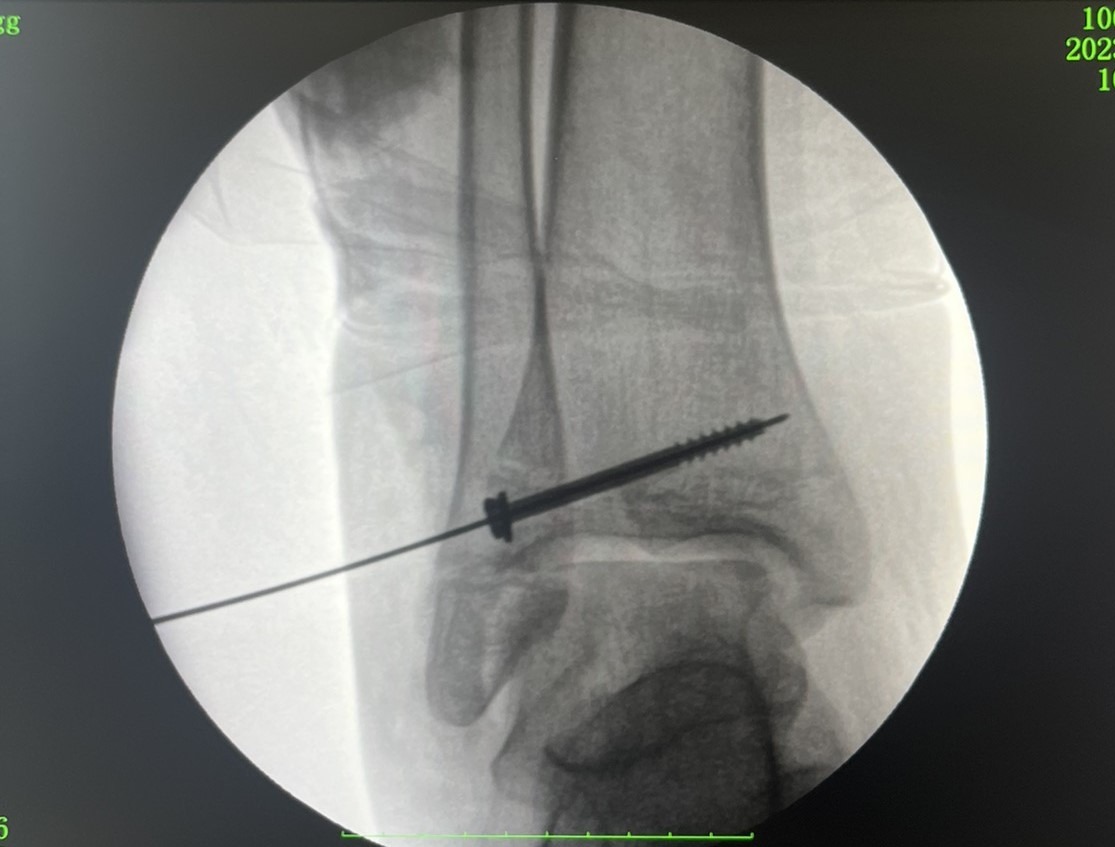

Зазначається, що для лікування перелому Тіллі застосовується методика відкритої репозиції та фіксації титановим гвинтом. Після операції повне відновлення функції гомілковостопного суглоба займає від 6 до 12 місяців.

Як виглядає нога після операції (фото: facebook.com/RivneODL)

У Рівному провели операцію дівчині з рідкісним переломом (фото: facebook.com/RivneODL)